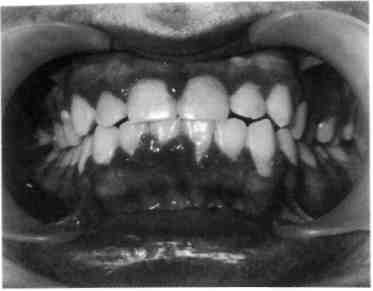

Хронический катаральный гин­гивит в стадии обострения характе­ризуется болевыми ощущениями, резкой спонтанной кровоточиво­стью десен. При этой форме воспа­ления десневого края часто отмеча­ется поражение всех трех участков десны. Из анамнеза можно устано­вить, что ребенок периодически страдал кровоточивостью десен и ранее (рис. 8.2; 8.3).

Рис. 8.2. Обострение хронического ка­тарального гингивита при лечении не­съемной ортодонтической техникой.

Рис. 8.3. Обострение хронического ка­тарального гингивита.